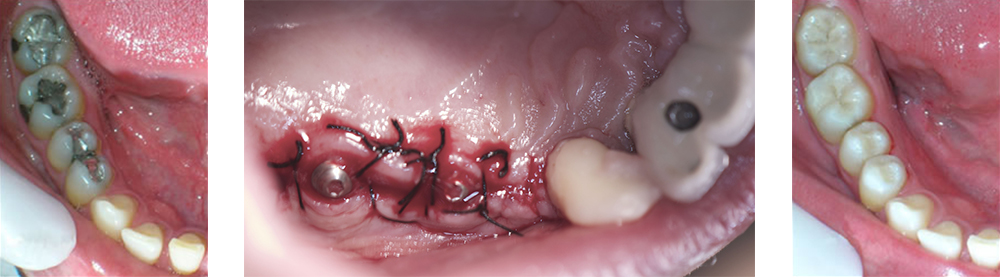

IMPLANTOLOGIA

Colocación de implantes y rehabilitación prótesica.